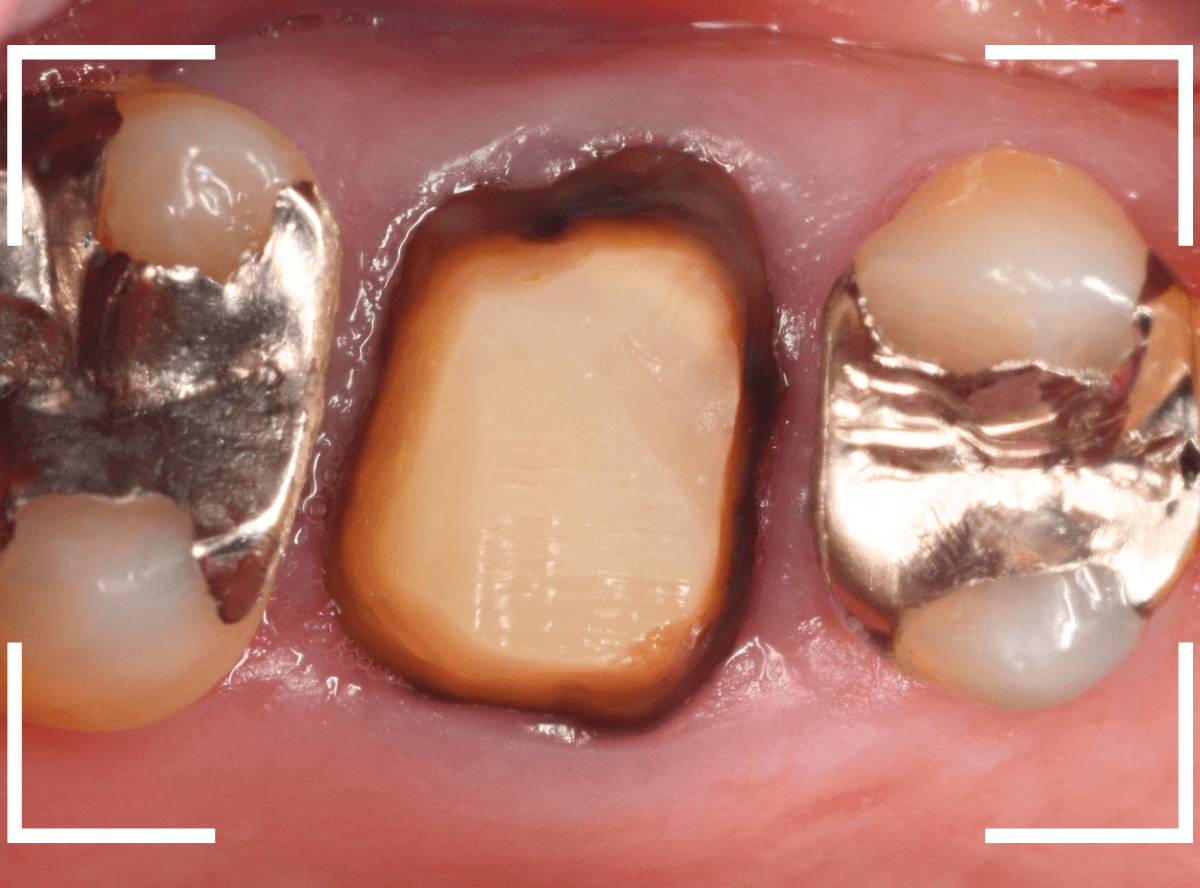

さし歯の土台の補修と、おやしらずの虫歯の処置をしたところです。

この状態で型をとります。

set後の写真です。

患者さんにも満足していただける仕上がりになりました。